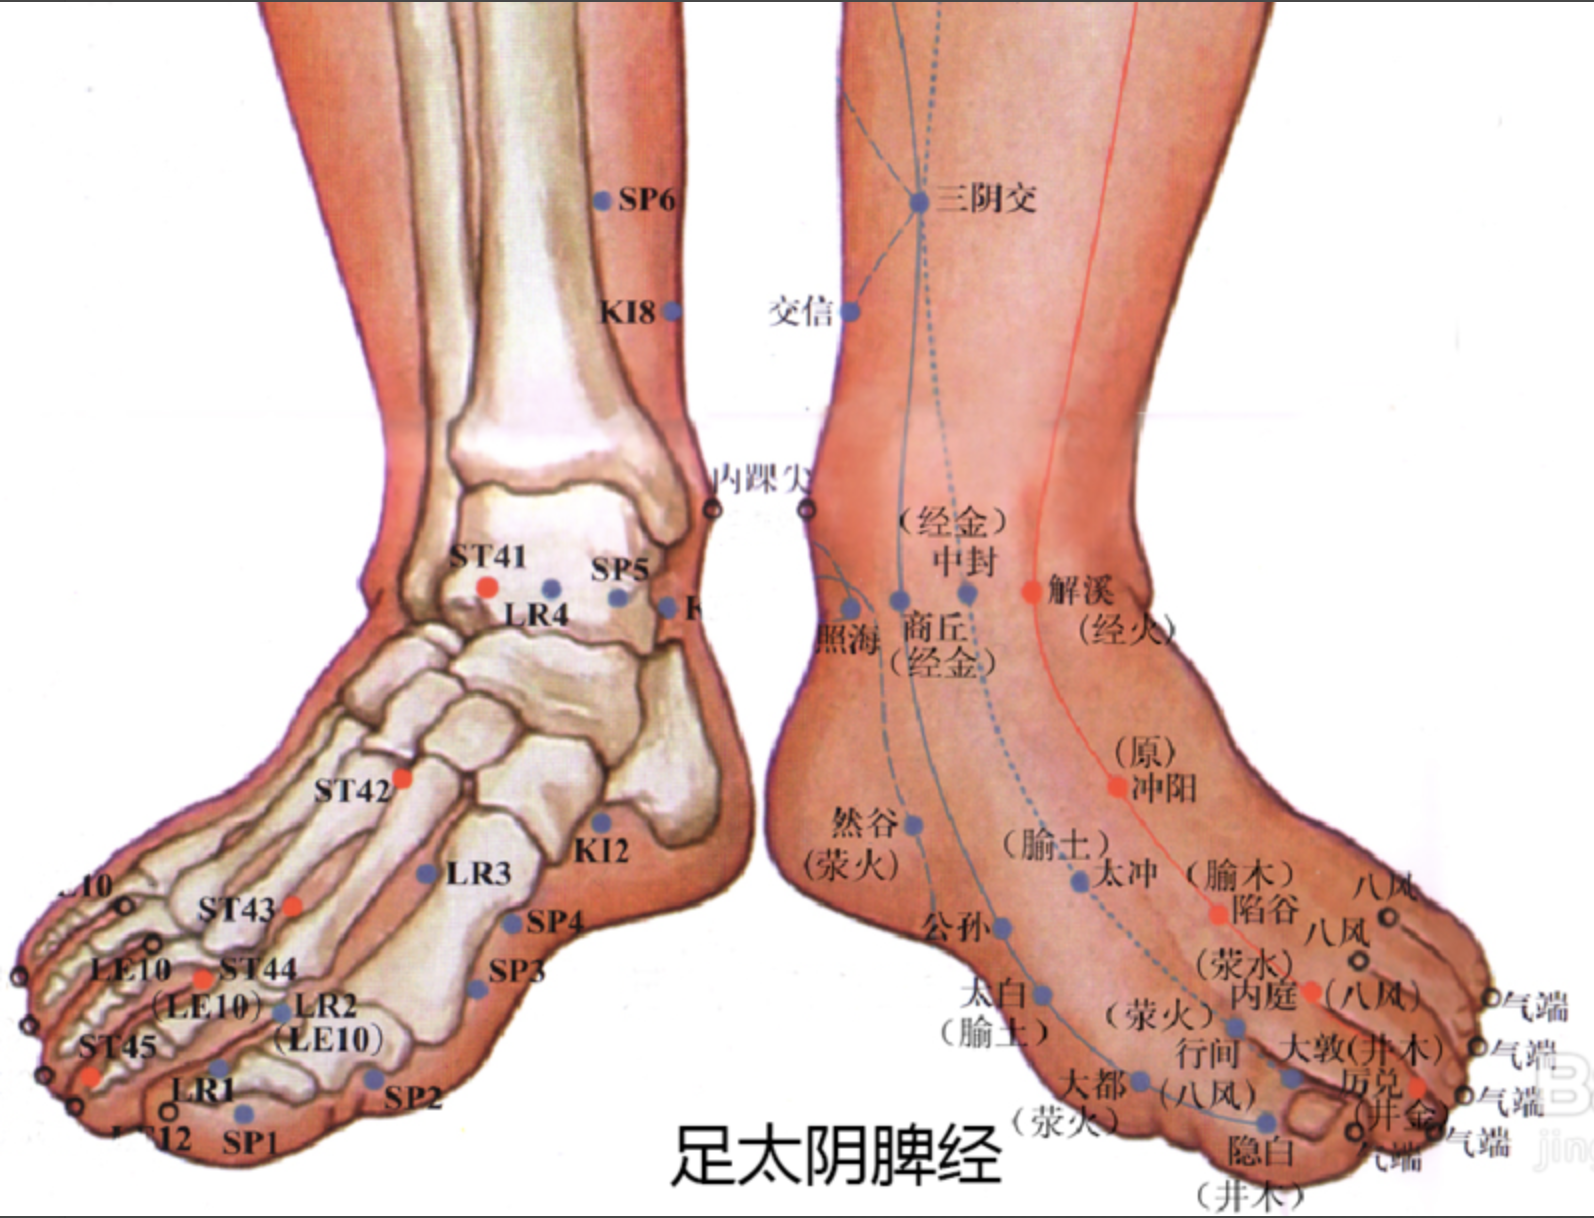

隐白

【定位】 在足大趾末节内侧,距趾甲角 0.1 寸(图 10-22-2)。

【主治】 腹胀,便血,尿血,月经过多,崩漏,癫狂,多梦,惊风。

【配伍】 配地机、三阴交治疗出血症。

【刺灸法】 浅刺 0.1 寸。

【附注】 足太阴经所出为“井”。

公孙

【定位】 在足内侧缘,当第 1 跖骨基底部的前下方(图 10-22-2)。

【主治】 胃痛,呕吐,腹痛,泄泻,痢疾。

【配伍】 配中脘、内关治胃酸过多、胃痛。

【刺灸法】 直刺 0.6 ~ 1.2 寸。

【附注】 足太阴经络穴:八脉交会穴之一,通于冲脉。参考资料:①据报道,对消化性溃疡病人进行 X 线胃肠检查时,观察到针刺内关、足三里对胃蠕动多有增强作用,尤以足三里为明显,而针刺公孙则胃蠕动多减弱。②据报道,针刺公孙、内关、梁丘等穴有抑制胃酸分泌作用。

三阴交

【定位】 在小腿内侧,当足内踝尖上 3 寸,胫骨内侧缘后方(图 10-22-3)。

【主治】 肠鸣腹胀,泄泻,月经不调,带下,阴挺,不孕,滞产,遗精,阳痿,遗尿,疝气,失眠,下肢痿痹,脚气。

【配伍】 配足三里治肠鸣泄泻,配中极治月经不调,配子宫治疗阴挺,配大敦治疝气,配内关、神门治失眠。

【刺灸法】 直刺 1 ~ 1.5 寸。

【附注】 (1)足太阴、少阴、厥阴经交会穴。(2)孕妇禁针。

阴陵泉

【定位】 在小腿内侧,当胫骨内侧髁(kē)后下方凹陷处。

【主治】 腹胀,泄泻,水肿,黄疸,小便不利或失禁,膝痛。

【配伍】 配肝俞、至阳治黄疸,阴陵泉透阳陵泉治膝痛。

【刺灸法】 直刺 1 ~ 2 寸。

【附注】 足太阴经所入为“合”。

血海

【定位】 屈膝,在大腿内侧,髌(bìn)骨内上缘上 2 寸,当股四头肌内侧头的隆起处(图 10-22-4)。

简便取穴:患者屈膝,医者以左手掌心按于患者右膝髌骨上缘,2 至 5 指向上伸直,拇指约呈 45 度斜置,拇指尖下是穴。对侧取法仿此。

【主治】 月经不调,崩漏,经闭,瘾疹,湿疹,丹毒。

【配伍】 配三阴交治月经不调,配曲池治瘾疹。

【刺灸法】 直刺 1 ~ 1.5 寸。